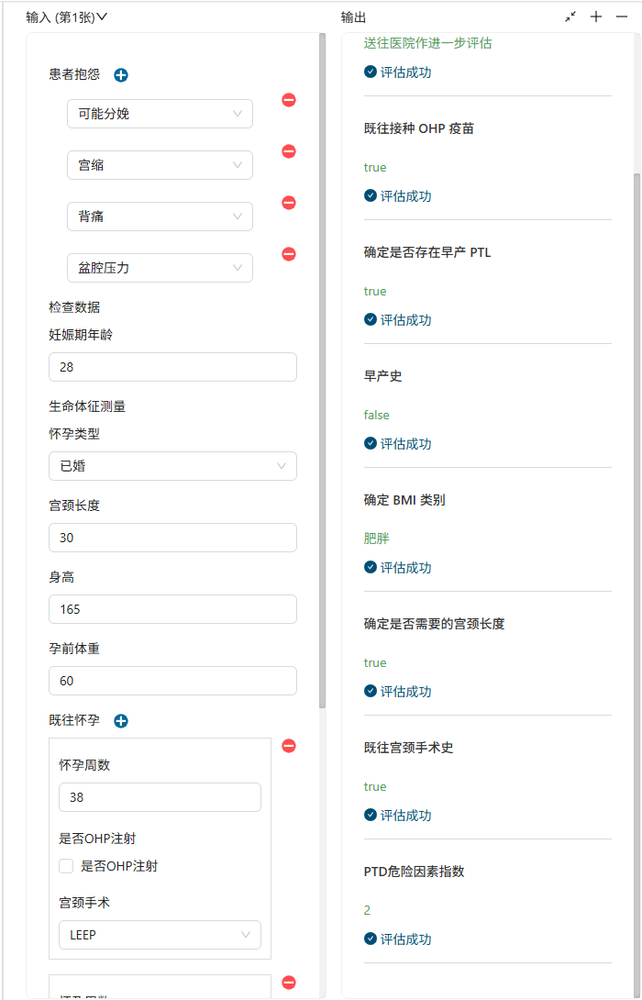

至此我们已经建立完成了“早孕诊断”的决策模型的构建,在Together建模器中打开测试表单,输入测试数据,我们得到一个诊断结果,与人类有经验的专业医生的诊断结果完全一样。

我们将“早孕诊断”决策模型与医院诊疗系统集成,可快速的算出诊断结果,由于医疗的严谨性、专业性,当然这将是一个建议方案,供医生确认后做为下一步治疗的依据。

通过测试用例,我们实现上述算法需求,业务系统只需简单的系统调用即可使用模型逻辑。我们还可以发布版本,快速迭代需求的变化。赶快联系我们,体验Together规则引擎强大功能吧!